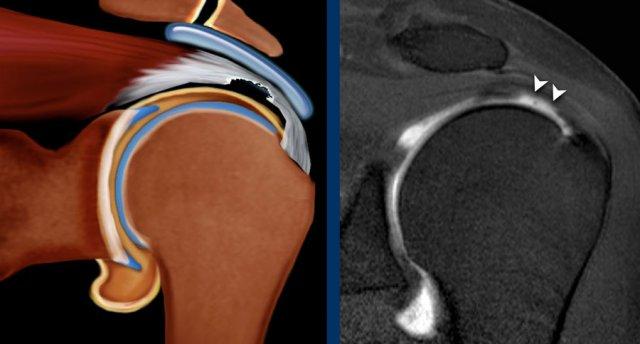

Hình ảnh

Hình minh họa và MRI khớp có thuốc tương phản từ chuỗi xung T1 xóa mỡ mặt phẳng coronal.